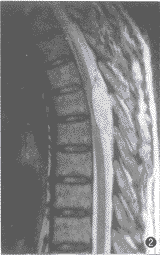

例1 男,65岁。下胸部束带感伴双下肢无力、行走不稳 4个月余。体检:T6以下浅感觉明显减退,双腹壁反射、提睾反射消失,双侧巴彬斯基征(+),双下肢肌力 IV级。脑脊液压力和常规检查正常。胸椎 X线片正常。 MRI扫描:T5~6水平椎管内脊髓后方硬膜外见一4.4 cm×1.5 cm大小的梭形病灶,基底靠后,最大处向两侧椎间孔方向生长。脊髓明显受压变细、前移。T1WI病灶与脊髓呈等信号(图1),T2WI上与脑脊液信号相似(图2)。注射钆喷替酸葡甲胺(Gd-DTPA)后,病灶呈明显均匀强化(图3)。MRI诊断:神经根瘤。手术所见:T5~6椎管内硬膜外见一肉红色梭形肿瘤,边界清楚,呈分叶状, 与硬脊膜有轻度粘连。未见明显增粗的供血动脉和引流静脉。邻近椎板和棘突骨质疏松,但无破坏。病理检查:肿瘤组织由大片壁薄、管腔扩大互相吻合、大小不一、外形不规则的血管间隙构成,壁为单层内皮细胞。血管间见散在的淋巴细胞和脂肪细胞(图4)。病理诊断:海绵状血管瘤。

图1~4 例1。 T1WI(图1)示 T5~6椎管内脊髓后方硬膜外梭形肿块与脊髓信号相等, 脊髓明显受压前移、变细,基底靠后。T2WI(图2)示病灶呈均匀高信号与脑脊液信号相似。注射钆喷替酸葡甲胺(Gd-DAPA)后(图3)病灶显著均匀强化。镜检(图4):肿瘤主要由扩张而大小不等的血管间隙构成,壁薄,由单层内皮细胞构成(HE 20×10)